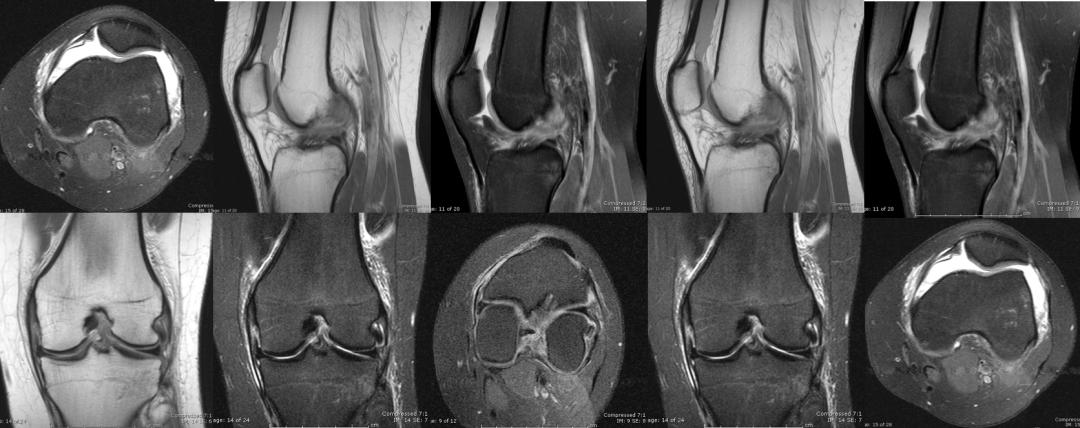

其实,X线和CT能看的主要是骨头,而MRI则主要看的是软组织。就像房子的钢筋水泥,质量过关,但住得舒不舒服装修也很重要。MRI就是帮你看看韧带、半月板等“软装”有没有问题的检查!

比如在打羽毛球时,一个扣杀好不精彩,但若是落地不慎,膝关节马上就让你无精打采,只能暂停一下,对比赛不理不睬。X线做完只告诉你没有骨折,但膝关节痛得让你实在没辙,只能再次来到影像科。膝关节MRI一做发现,前交叉韧带断了!

前交叉韧带能断,后交叉韧带一样也有可能被扯断。比如一不小心跌倒,膝盖没跪碎,但却有可能把后交叉韧带给跪断。骑着电瓶车在马路上摔倒,一下子膝盖敲到了地上,不少叔叔阿姨的韧带就是这样断了。类似的损伤同样可以通过膝关节MRI来诊断。这不,一做就发现,后交叉韧带真的会断!

除了韧带可能在运动中被扯断、撞坏之外,膝关节里还有两块半月板也很容易受伤。就像坐在硬板凳上屁股硌得难受一样,膝关节上下两个大骨头要是直接硬碰硬,你的膝关节肯定不会好受。而半月板就像两块缓冲垫,能让股骨和胫骨和谐共处,你的膝关节也能正常发挥功能。不过,如果半月板出现了损伤,那你的膝关节可能就不会那么灵活,蹲下站起可能会“咔咔”响,甚至有时好像卡住了一样。这时,MRI也是诊断的重要工具,如果真的存在半月板撕裂,在膝关节MRI上就能看到半月板“裂开”了。

膝关节的X光平片是膝关节疾病的首选检查。如果有理由怀疑骨折,那么选择CT也很有帮助。不过,膝关节是目前最常应用MRI检查的关节,MRI评估半月板、韧带、关节软骨等结构已经有了广泛的研究,已经成为了评估半月板和韧带损伤的标准技术。除了运动受伤有可能需要做个膝关节MRI之外,中老年人在膝关节疼痛时也常能在MRI上发现各种膝关节“年纪大了”所导致退行性改变。

膝关节是人体内最复杂、损伤最多的关节。膝关节X线及CT检查主要用于除外骨性结构损伤,MRI在评估半月板、韧带、肌腱和关节软骨具有重要价值。当然,除了根据需要选择适当的检查之外,更重要的是请专业的影像科医生来诊断。